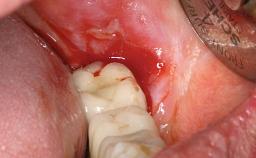

Biological complications caused by undetected cement residue have been receiving much attention. Excess cement might be responsible not only for rapidly developing of peri-implantitis, but also for delayed or chronic manifestations of the disease many years after cementation (Wilson 2009; Linkevicius and coworkers 2013). Invitro and clinical studies have shown that it is very difficult or even impossible to completely clean up excess cement at subgingival margins, so popular in cemented restorations (Agar and coworkers 1997; Linkevicius and coworkers 2011, 2012). Possible outcomes of biological complications due to excess cement range from temporary inflammation of the peri-implant soft tissues without any serious esthetic and functional consequences all the way to implant loss. This report describes a case of peri-implantitis caused by residual cement; as well as the management and quite unusual resolution of the complication. The patient presented in 2009 with a draining sinus tract, tenderness on chewing, and tissue contact above the implant-supported restoration. The implant had been restored approximately three years before.